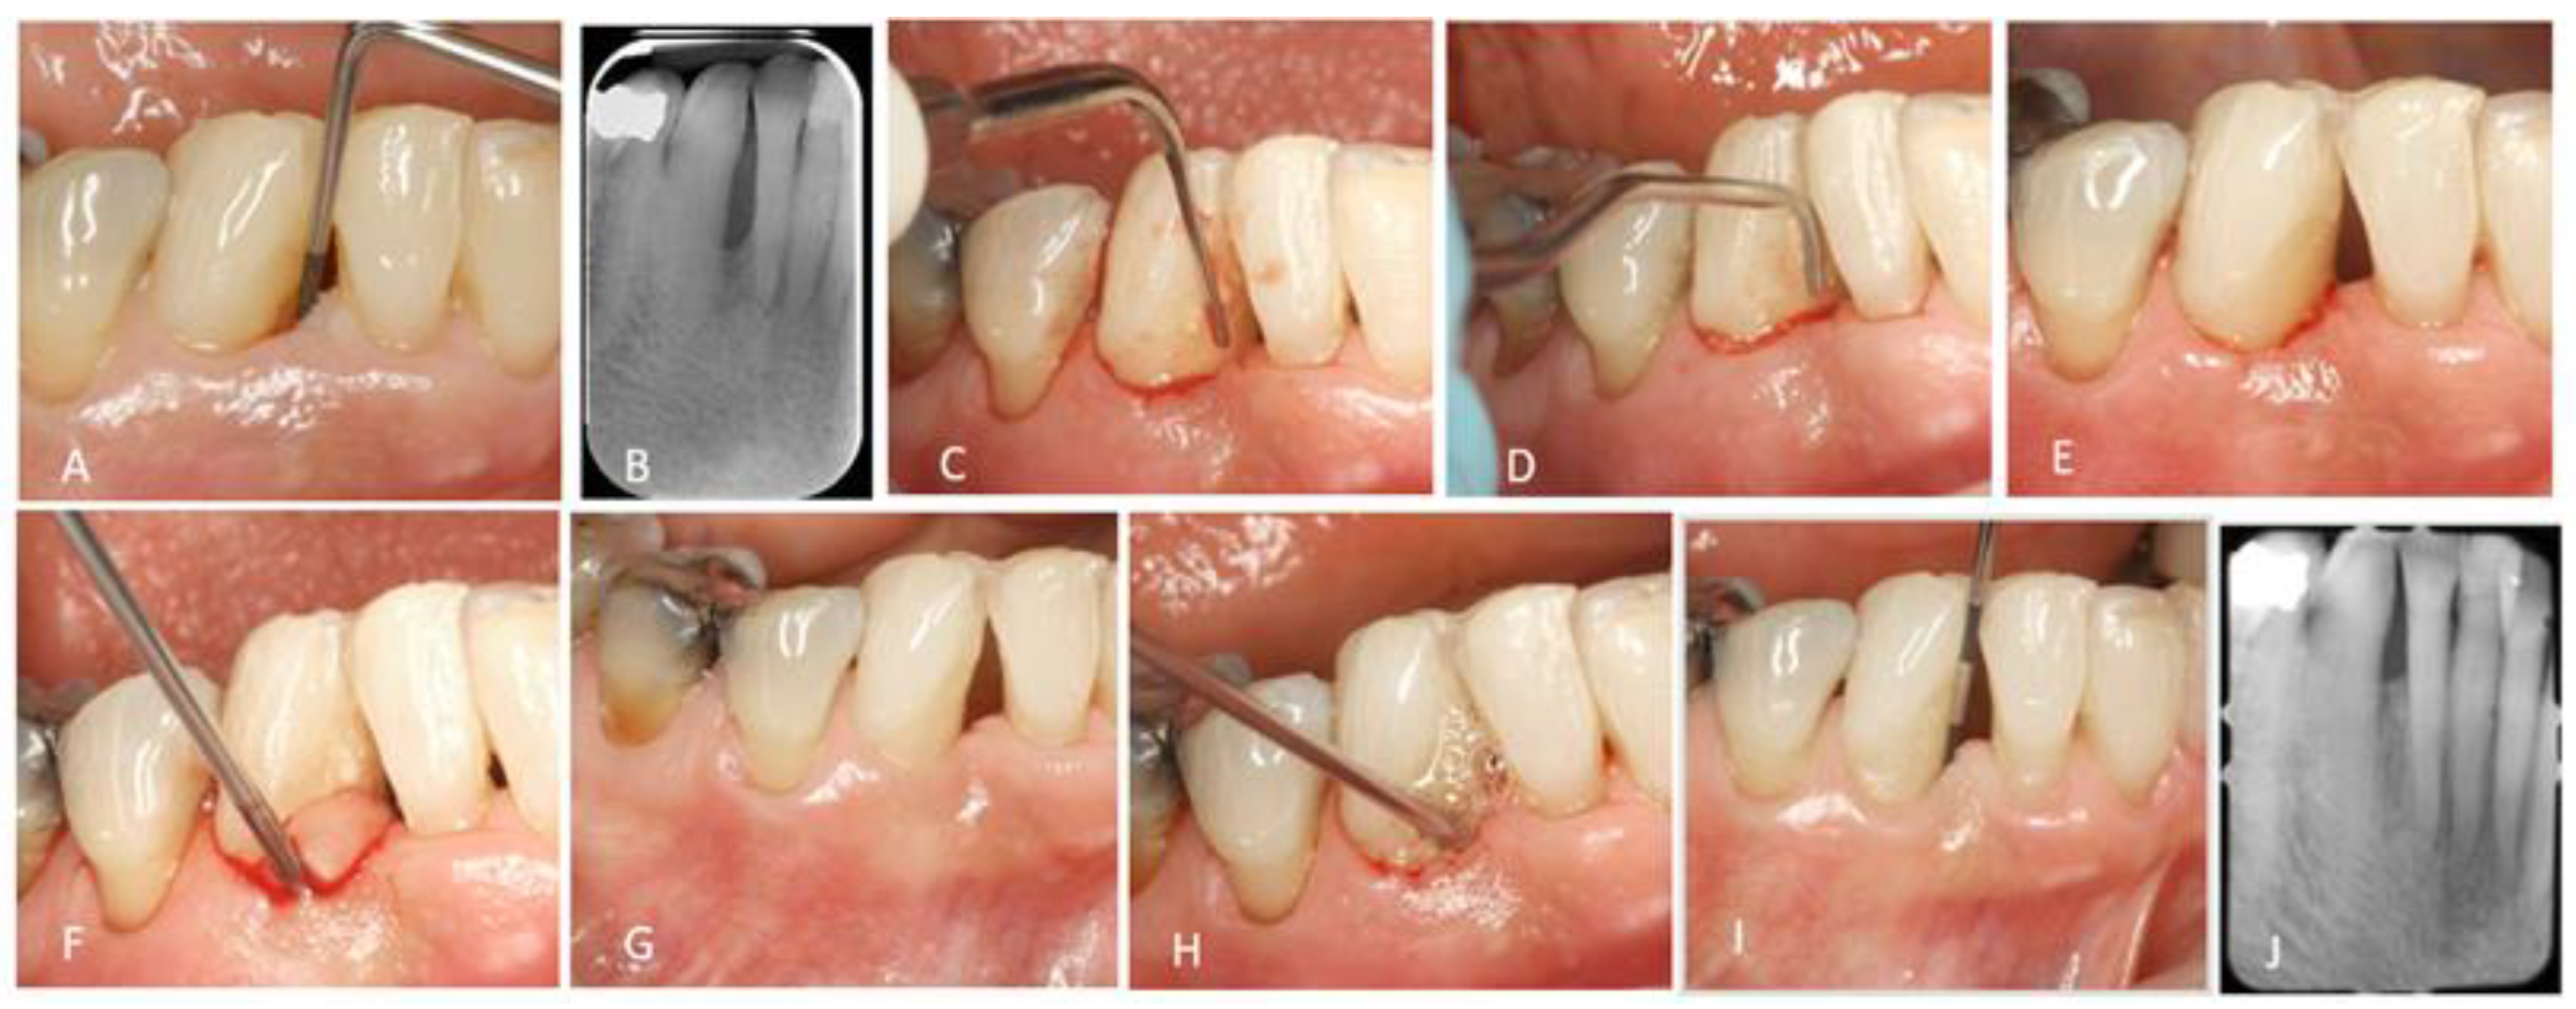

2. Surgical Treatment of Intrabony Defects

3. Minimally Invasive Non-Surgical Technique